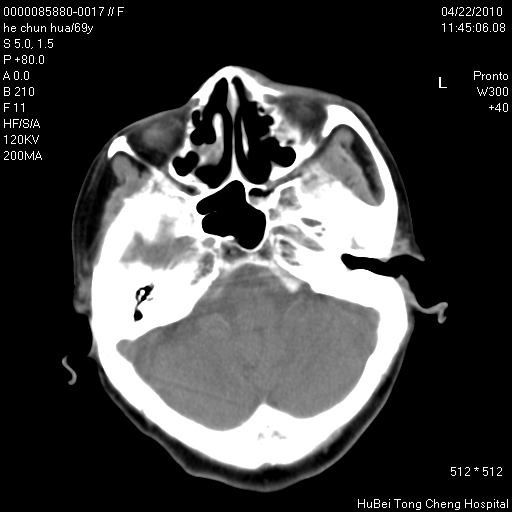

标题: CT25937:女,69Y

硬腭部包块十余年,渐进性增大。

不管以前,现在是恶性占位了

支持硬腭部恶性肿瘤!

硬腭部肿瘤恶变可能。

硬腭占位 恶性可能性大

考虑硬腭部肿瘤恶变可能。